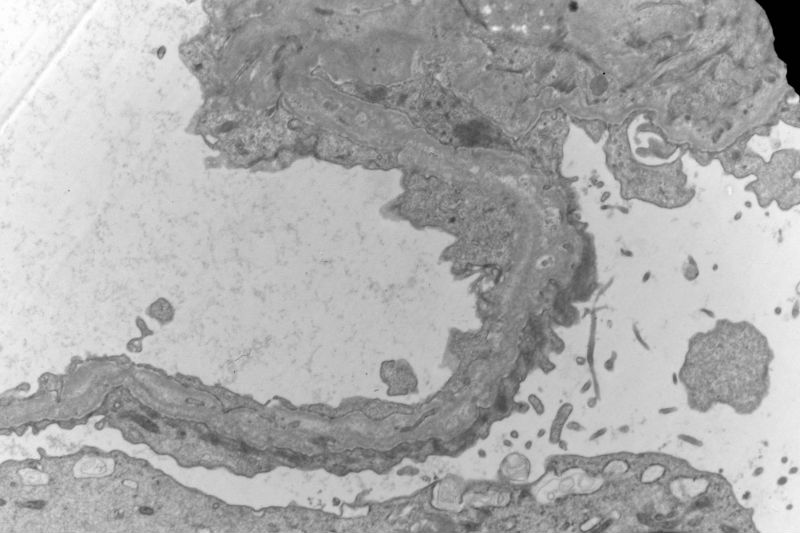

Sixty old man with proteinuria and hematuria

Yes, I agree with your observation that there are a lot of foamy cells. The most impressive change is the lamination or splitting of the glomerular basement membrane.

Thank you,to combine the splitting of the glomerular basement membrane with a lot of foamy cells infiltration, I first take into account Alport Syndrome, but the age of the patient is too old, so Alport Syndrome seems unlikely. Under LM, the glomerulosclerosis and tubular atrophy/interstitial fibrosis. Please comment, thank you

The patient has a long history of "chronic kidney disease". Initially, he did not tell the nephrologist that he started to have kidney disease decades ago. Given the characteristic ultrastructural changes, Alport's syndrome is suggested.